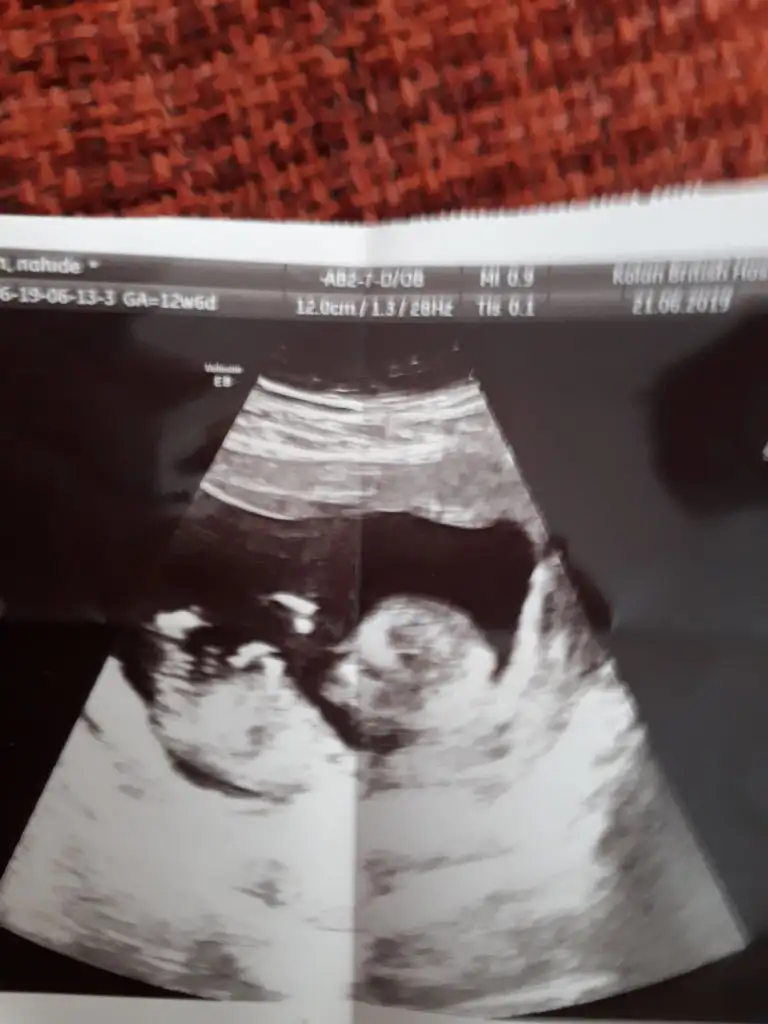

Nub yöntemine göre cinsiyet tahmini

Gittim canim dr kiz gibi dedi ama kesin soyleyebilmem icin 16.haftayi bekleyecegiz dedi ama nubu bana gore karsiya bakiyor onda da kesin konusmadi erkek olsa yanilma olmaz bu haftalarda ama bazen kizda yanilma olabilir bekleyelim dedi

Canım bencede kız.diğer nub teorisinde de belliydi.hatta sana kesin kız demiştim.nubu bariz paraleldi.ben öyle gördüm yani.şimdi bi kızın olduğu için eşinde sende erkek bebek istiyorsunuz tabi,insan olmayanı istiyor her zaman.ama bana göre cok şanslısın.kız cocuğu rahmettir,berekettir.benimde bi kızım var.keza senin de öyle.ne denli tatlılar biliyoruz.şükürler olsun yaradana.

Kesin kız canım o bebiş, doktorda söylerken emin bi şekilde söylemiş.anneolmakmucızenin en son ki mesajında öyle yazıyor. Nub bariz paralel. 😁😁 olabilir arada yanılabiliriz sıkıntı yok🤗